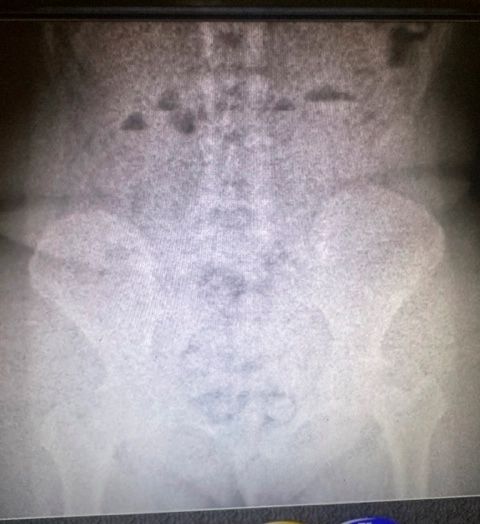

En la primera revisión del equipaje de las mujeres no se encontraron resultados positivos, sin embargo, con la autorización del Juzgado Nacional en lo Penal Económico N°7, una requisa personal, junto con un body scan descubrieron la presencia de estupefacientes.

Así, las pasajeras fueron trasladadas al hospital interzonal de Ezeiza, detenidas e incomunicadas, donde, al cabo de su internación, se constató que una de ellas llevaba nada menos que 946 gramos de cocaína en su organismo y la otra, 823 gramos.

Así, el total de la droga encontrada asciende a 1.769 gramos. En los términos establecidos por el artículo 866 del Código Aduanero, las mujeres podrían enfrentar penas de hasta 12 años de prisión, cada una.